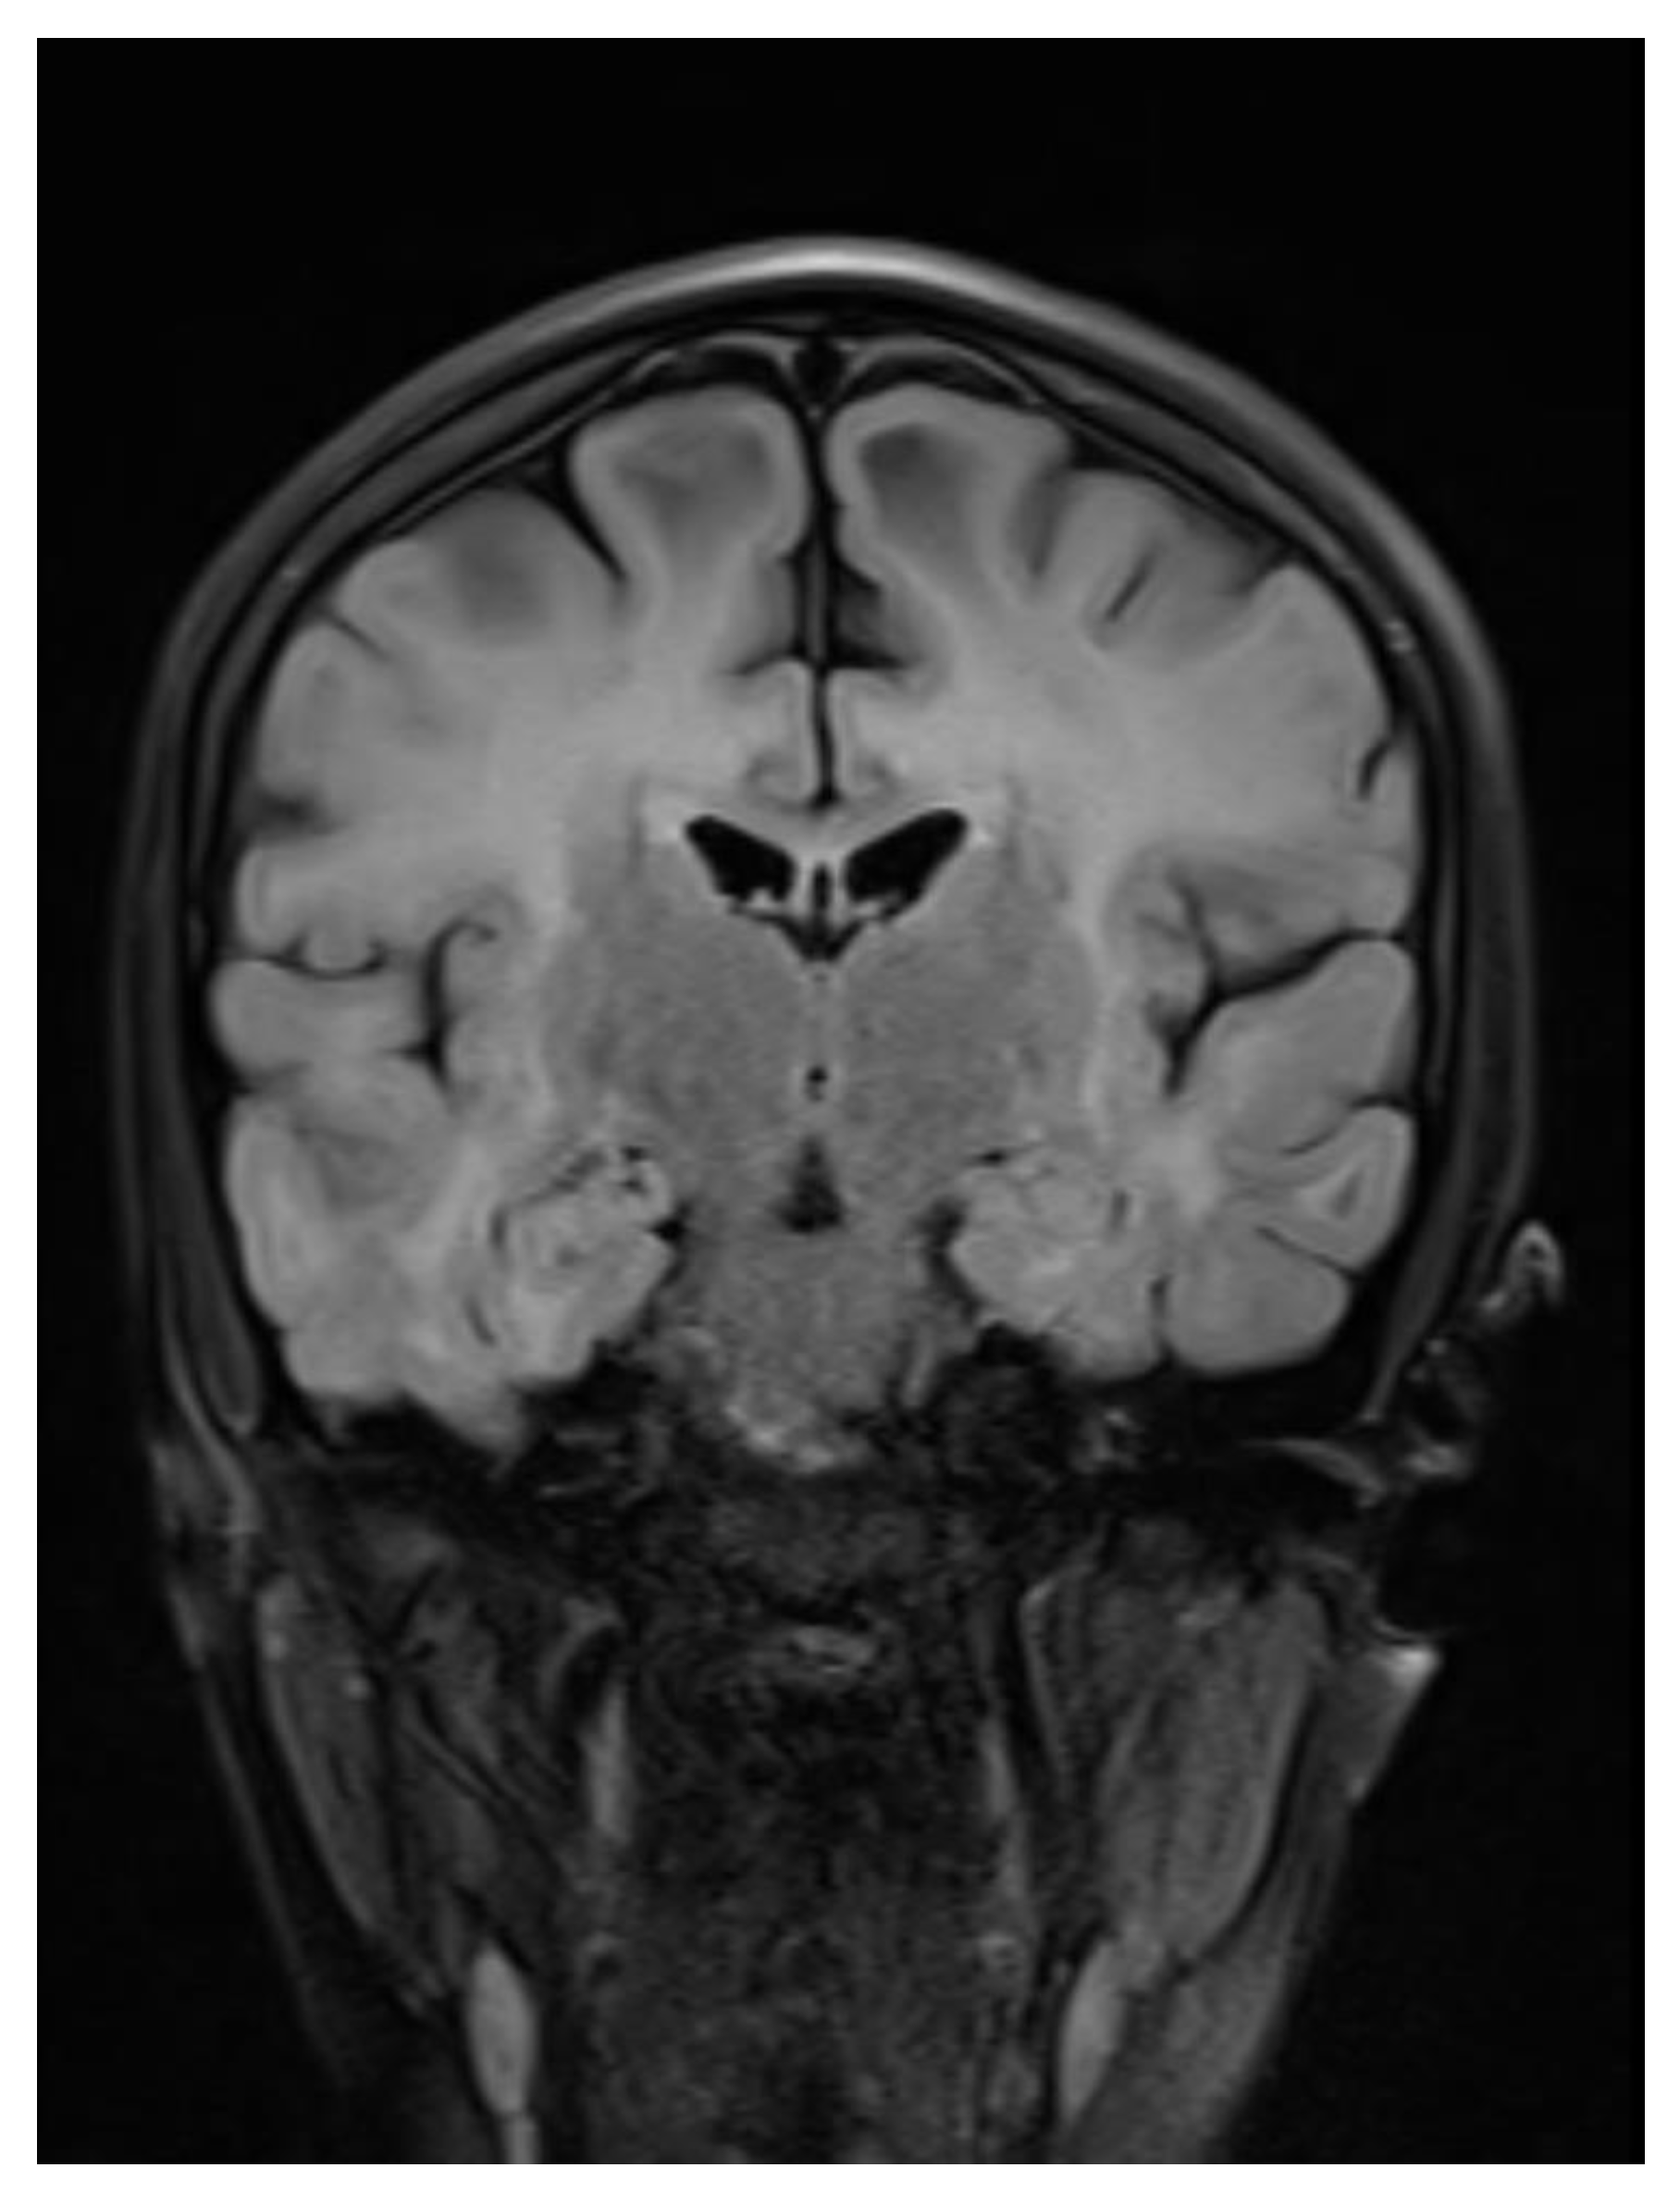

A contrast-enhanced MRI of the brain was performed, bilateral symmetrical diffuse abnormal T2WI/FLAIR hyperintensity involving the subcortical and periventricular deep white matter of bilateral cerebral hemispheres and corpus callosum with areas of diffuse restriction in bilateral centrum semi-ovale restriction, subcortical cysts, and cerebral atrophy were seen with possibility of Megalencephalic leukoencephalopathy with subcortical cysts also known as Van der knap disease. Post-contrast imaging showed normal enhancement, ruling out vascular abnormalities or abnormal enhancement patterns.

Figure 3. Axial flair images showing Bilateral symmetrical white matter hyperintensity with subcortical cyst formation in the left frontal lobe.

The clinical and radiological findings were consistent with megalencephalic leukoencephalopathy with subcortical cysts, also known as Van der Knaap disease.